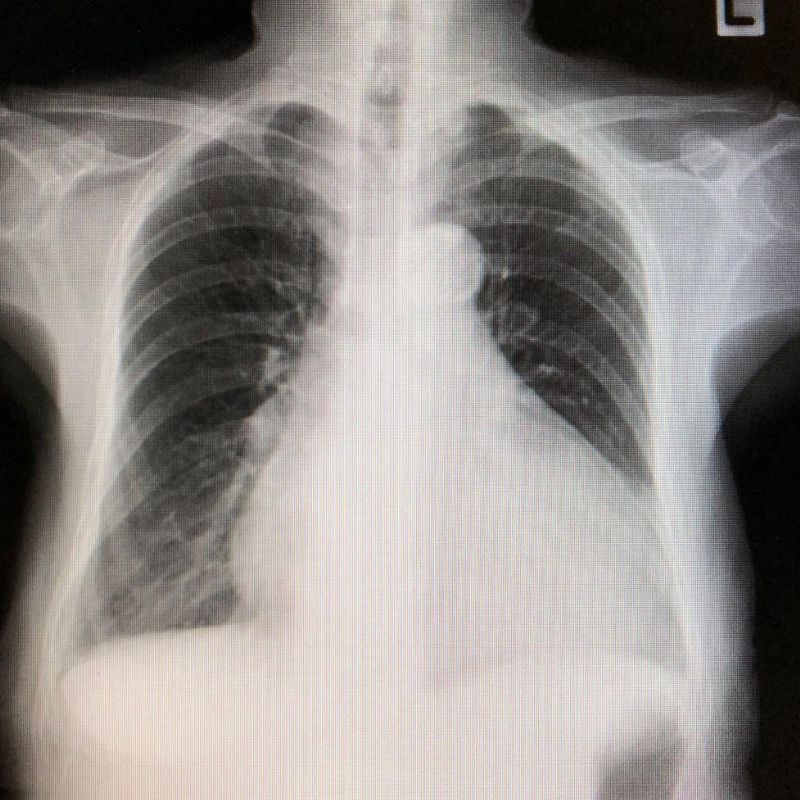

Dưới đây là một số hình ảnh hở van tim hai lá, giúp bạn hiểu rõ hơn về bệnh lý này:

Chụp X-quang ngực dùng tia X có bức xạ cao, cung cấp hình ảnh cấu trúc tim, phổi. Kỹ thuật này nhằm tìm kiếm các biểu hiện hở tim van 2 lá như bóng tim to, giãn nhĩ trái, giãn thất trái, sung huyết phổi, phù phổi (tích tụ dịch trong phế nang) do suy tim.

Cụ thể, siêu âm tim giúp đánh giá mức độ hở van 2 lá; đánh giá chức năng thất trái; áp lực động mạch phổi. Đo điện tâm đồ nhằm theo dõi rối loạn nhịp tim liên quan đến hở van. Chụp X-quang để xác định giãn nhĩ trái, thất trái, tích tụ dịch trong phổi.